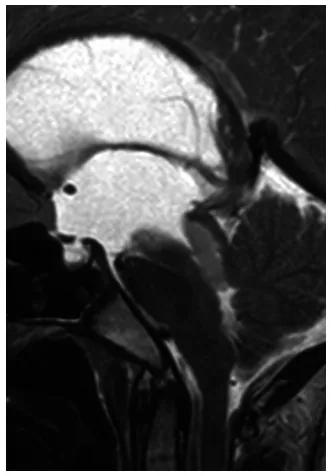

作为母亲,我从未预料到一场看似普通的“小毛病”竟会让我们陷入与死神赛跑的境地。“妈妈,我头痛剧烈!”那是一个平常的日子,12岁的儿子昭昭开始主诉头痛,并伴有间歇性恶心。起初,我们误以为是季节变化引起的感冒或饮食问题,医生也按病毒性感冒开具了止痛药和止吐药。然而第二天清晨,患儿趴在马桶边呕吐不止,无法直起身子,并持续抱怨头痛难忍。身为母亲,目睹此景我立即带他前往医院并办理住院手续。“需要进行脑部检查?”我半信半疑地询问医生,并非不信任医疗建议,而是不愿接受孩子颅内患病的事实。MRI检查结果出来后,我几乎无法站立。医生告知,第三脑室后部存在一个源于中脑顶盖的强化病灶,正好堵塞了脑脊液循环通道中脑导水管,已形成梗阻性脑积水(图1)。

图1. 矢状位T2加权MRI图像显示第三脑室后部导水管入口处病灶。